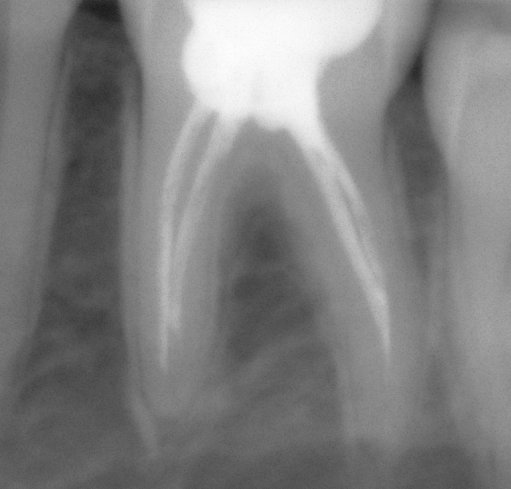

Здравствуйте! У меня гранулематозный периодонтит. 46 зуб. Полгода назад уже удалила 36 зуб из-за неудачного и бесполезного бесплатного лечения в поликлинике. Сейчас лечу в частной стоматологической клинике. 2 раза закладывали лекарство на 2 недели. Прошел месяц, сделали снимок, воспаление все равно держится.

Необходимо понять размеры грануляции, чтобы однозначно поставить диагноз о методах лечения.